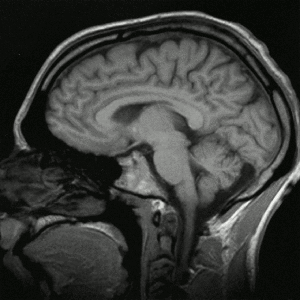

Schnitt – von (Nase) vorne |

Das am weitesten innenliegende sogenannte 'Stammhirn' (oder Hirnstamm) des Menschen, gilt als der am vielfältigsten zusammengesetzte und uneinheitlichste, der vereinfachend zusammenfassenden vier Teilbereich (so dass diese Begrifflichkeit zugunsten genauerer kleinräumlicherer Bezeichnungen verdrängt werden mag). |

Neben dem, grob gesprochen, die (teils 'bewusst', will heissen vom Menschen reflektierend bemerkt) 'denkenden' Grosshirnhälften untereinander und mit dem (die Feinmotorik des Menschen steuernden und das räumlich Gleichgewicht sichernde) Kleinhirn (Cerebellum) sowie dem (überwiegend die 'Nervensteuerung' mit der 'Hormonsteuerung' koppelnde), 'Zwischenhirn' (Diencephalon) verbindenden 'unteren, längs' Brücke (Pons), wird meist auch das (wohl Sinneseindrücke an's 'Gedächtnis' vermittelnde) 'Mittelhirn' (Mesencephalon) und die, von unten her in den Schädelraum reichende, Verlängerung des Rückenmarks (Medulla oblongata) zum Hinstamm 'gezählt' ... |